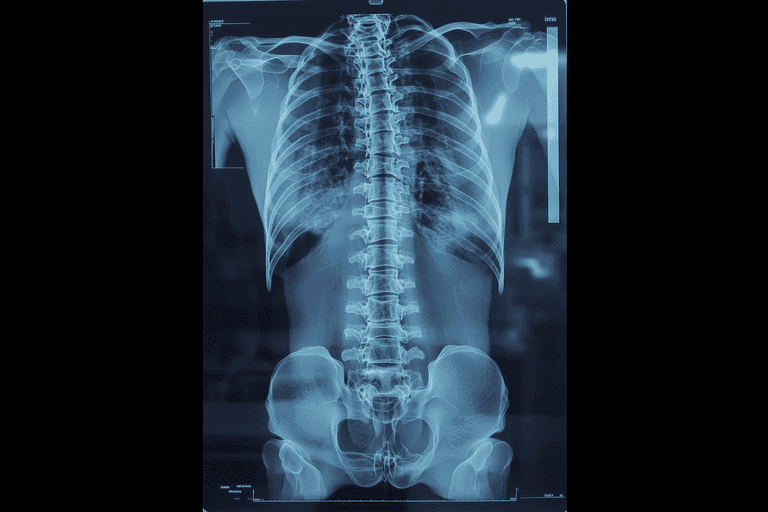

Marshall Deltoff DC, DACBR, FCCR(C) graduated with honors from the Canadian Memorial Chiropractic College in Toronto. He has over 30 years of academic, clinical and regulatory experience, having performed and read over 140,000 plain film x-ray examinations. He is the co-author of The Portable Skeletal X-Ray Library, a textbook of radiological bone diseases, as well as several book chapters, manuscripts and research papers and was selected to assist Yochum, T. & Rowe, L. in the final editorial process of textbook: “Essentials of Skeletal Radiology”. Dr. Deltoff has served as the President of the College of Chiropractors of Ontario, the regulatory body for over 5,000 DCs in that province. Currently, he is Professor of Radiology at Barcelona College of Chiropractic, and manages Images Radiology Consultants, an online x-ray reporting service for colleagues worldwide.